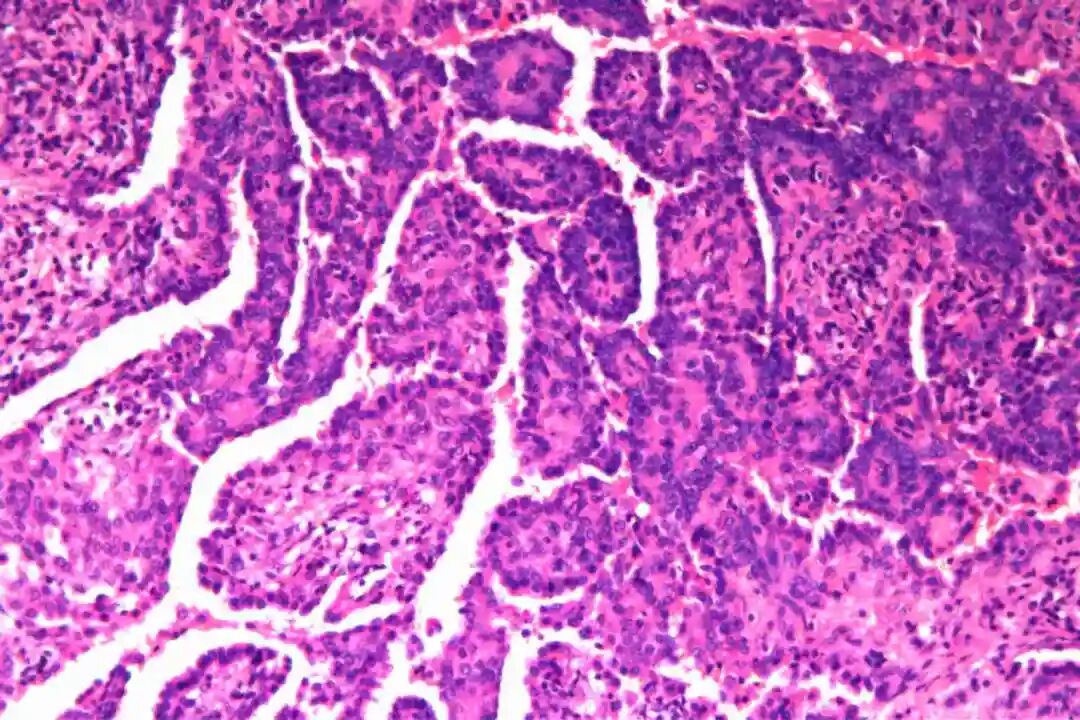

镜下特征:

细胞形态:两种独特的细胞类型,即表面立方细胞和间质圆形细胞。表面立方细胞通常呈立方形或低柱状,细胞核圆形或椭圆形,染色质细腻且分布均匀,核仁不明显或较小。细胞质丰富,呈嗜酸性,有时可见细小的颗粒状物质。间质圆形细胞则具有较大的核质比,细胞核多为圆形或卵圆形,染色质较深,核仁清晰可见。细胞质较少,呈淡嗜酸性或透明状,部分细胞可表现出一定的多形性。

组织特征:包括硬化区、出血区、实性区和乳头状区四种典型形式。硬化区由大量胶原纤维组成,其间散在分布着间质圆形细胞,这些细胞常围绕血管或呈片状排列。出血区则以红细胞积聚为特征,伴有泡沫状巨噬细胞和含铁血黄素沉积,周围可见表面立方细胞形成的血管样结构。实性区由密集的间质圆形细胞构成,细胞排列成片状或巢状,其间可见少量表面立方细胞覆盖的小管状结构。乳头状区最为复杂,其核心由纤维血管轴组成,表面被覆一层或多层表面立方细胞,周围环绕间质圆形细胞。这四种结构在肿瘤中往往以不同的比例混合存在,形成了PSP独特的病理景观。